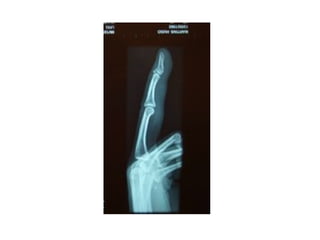

INCIDÊNCIAS PUNHO E MÃO

• #5 3 razões: lembrar que a radiografia se dá em um único plano e, portanto, mais de um plano é importante para se ter certeza que a lesão existe ou não (já que esta pode aparecer em uma incidência, mas não na outra) e para determinar o alinhamento das fraturas. Aqui está o link para se falar de posicionamento

• #6 A mesma fratura. Uma vista em ap e outra em perfil. Isso mostra que a mesma imagem toma formas diferentes dependendo da incidência. Por isso é importante ter duas incidências no mínimo, pois elas se complementam